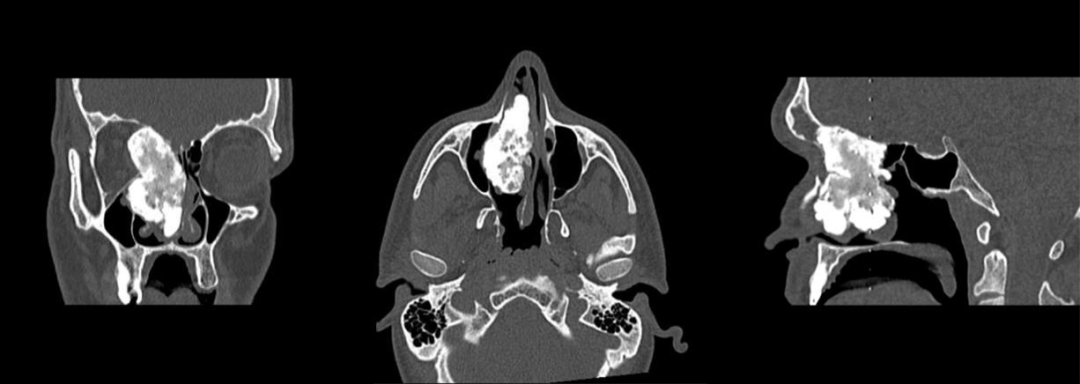

骨纤维异常增殖症 X 线表现因纤维组织增生程度、骨样组织、新生骨小梁含量及成熟程度的不同而呈不同改变,主要征象包括:

1. 磨玻璃样改变:56% ;2. 均匀硬化:23%;3. 囊性改变:21%;4. 膨胀性改变;5. 丝瓜瓤样改变

磨玻璃样及囊性改变

硬化性改变

膨胀性改变

丝瓜瓤样改变